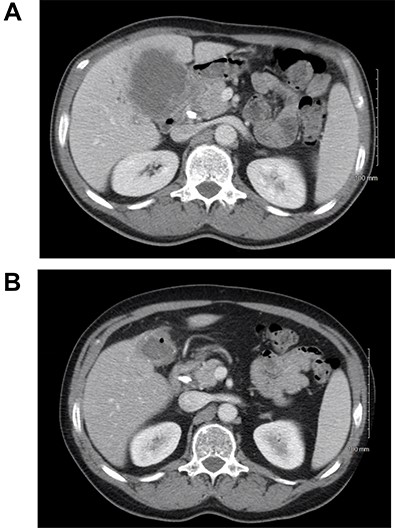

A 59-year-old male presented with abdominal pain for several months. Computed tomography (CT) showed a 9.3-cm gallbladder mass with direct extension into the right and left hepatic lobes (Fig. 1A), porta hepatis and mesenteric fat. Biopsy established a poorly differentiated adenocarcinoma of gallbladder origin. Biliary obstruction at the level of the common and cystic duct junction was managed with internal biliary stenting. The process presented as cT3N1M0, locally advanced, and not completely resectable gallbladder adenocarcinoma; serum CA 19–9 level was 2666 U/ml (normal up to 35 U/ml).

(A) CT scan of the abdomen showing the thickened gallbladder as well as a mass involving hilar hepatic parenchyma; (B) treatment response after immunotherapy.

The patient received systemic chemotherapy with gemcitabine and cisplatin. After more than 2 months, he developed grade 3 neuropathy and experienced several episodes of cholangitis with liver abscess and bacteremia requiring multiple stent exchanges, and systemic therapy was discontinued. He then received trial-based immune check point inhibition with ipilimumab and nivolumab. There was good radiological (Fig. 1B) and tumor marker response (CA 19–9 7.05 U/ml). Immunotherapy had to be stopped after 10 months due to grade 3 autoimmune hepatitis. He was treated with oral steroids and immunosuppression with mycophenolate mofetil, resulting in the normalization of liver function tests. A R0 resection was now deemed a possibility, with a goal of best tumor control and long-term biliary decompression. He underwent right portal vein embolization after which his left lobe future liver remnant grew from 28 to 45% at a kinetic growth rate of 5.6% per week (Fig. 2). He underwent extended right hepatectomy with radical cholecystectomy, portal and hepatic artery lymph node dissection, and Roux-Y hepaticojejunostomy biliary reconstruction (Fig. 3). Pathology examination revealed a 6.5-cm gallbladder and hepatic tissue mass with xanthogranulomatous inflammation and nodular fibrosis, without residual viable tumor, margins free of carcinoma and 0/17 lymph nodes involved, consistent with an ypT0N0M0 gallbladder cancer, R0 resection. After an initial postoperative surgical site infection, he has now fully recovered and is disease-free at 10-month follow-up.